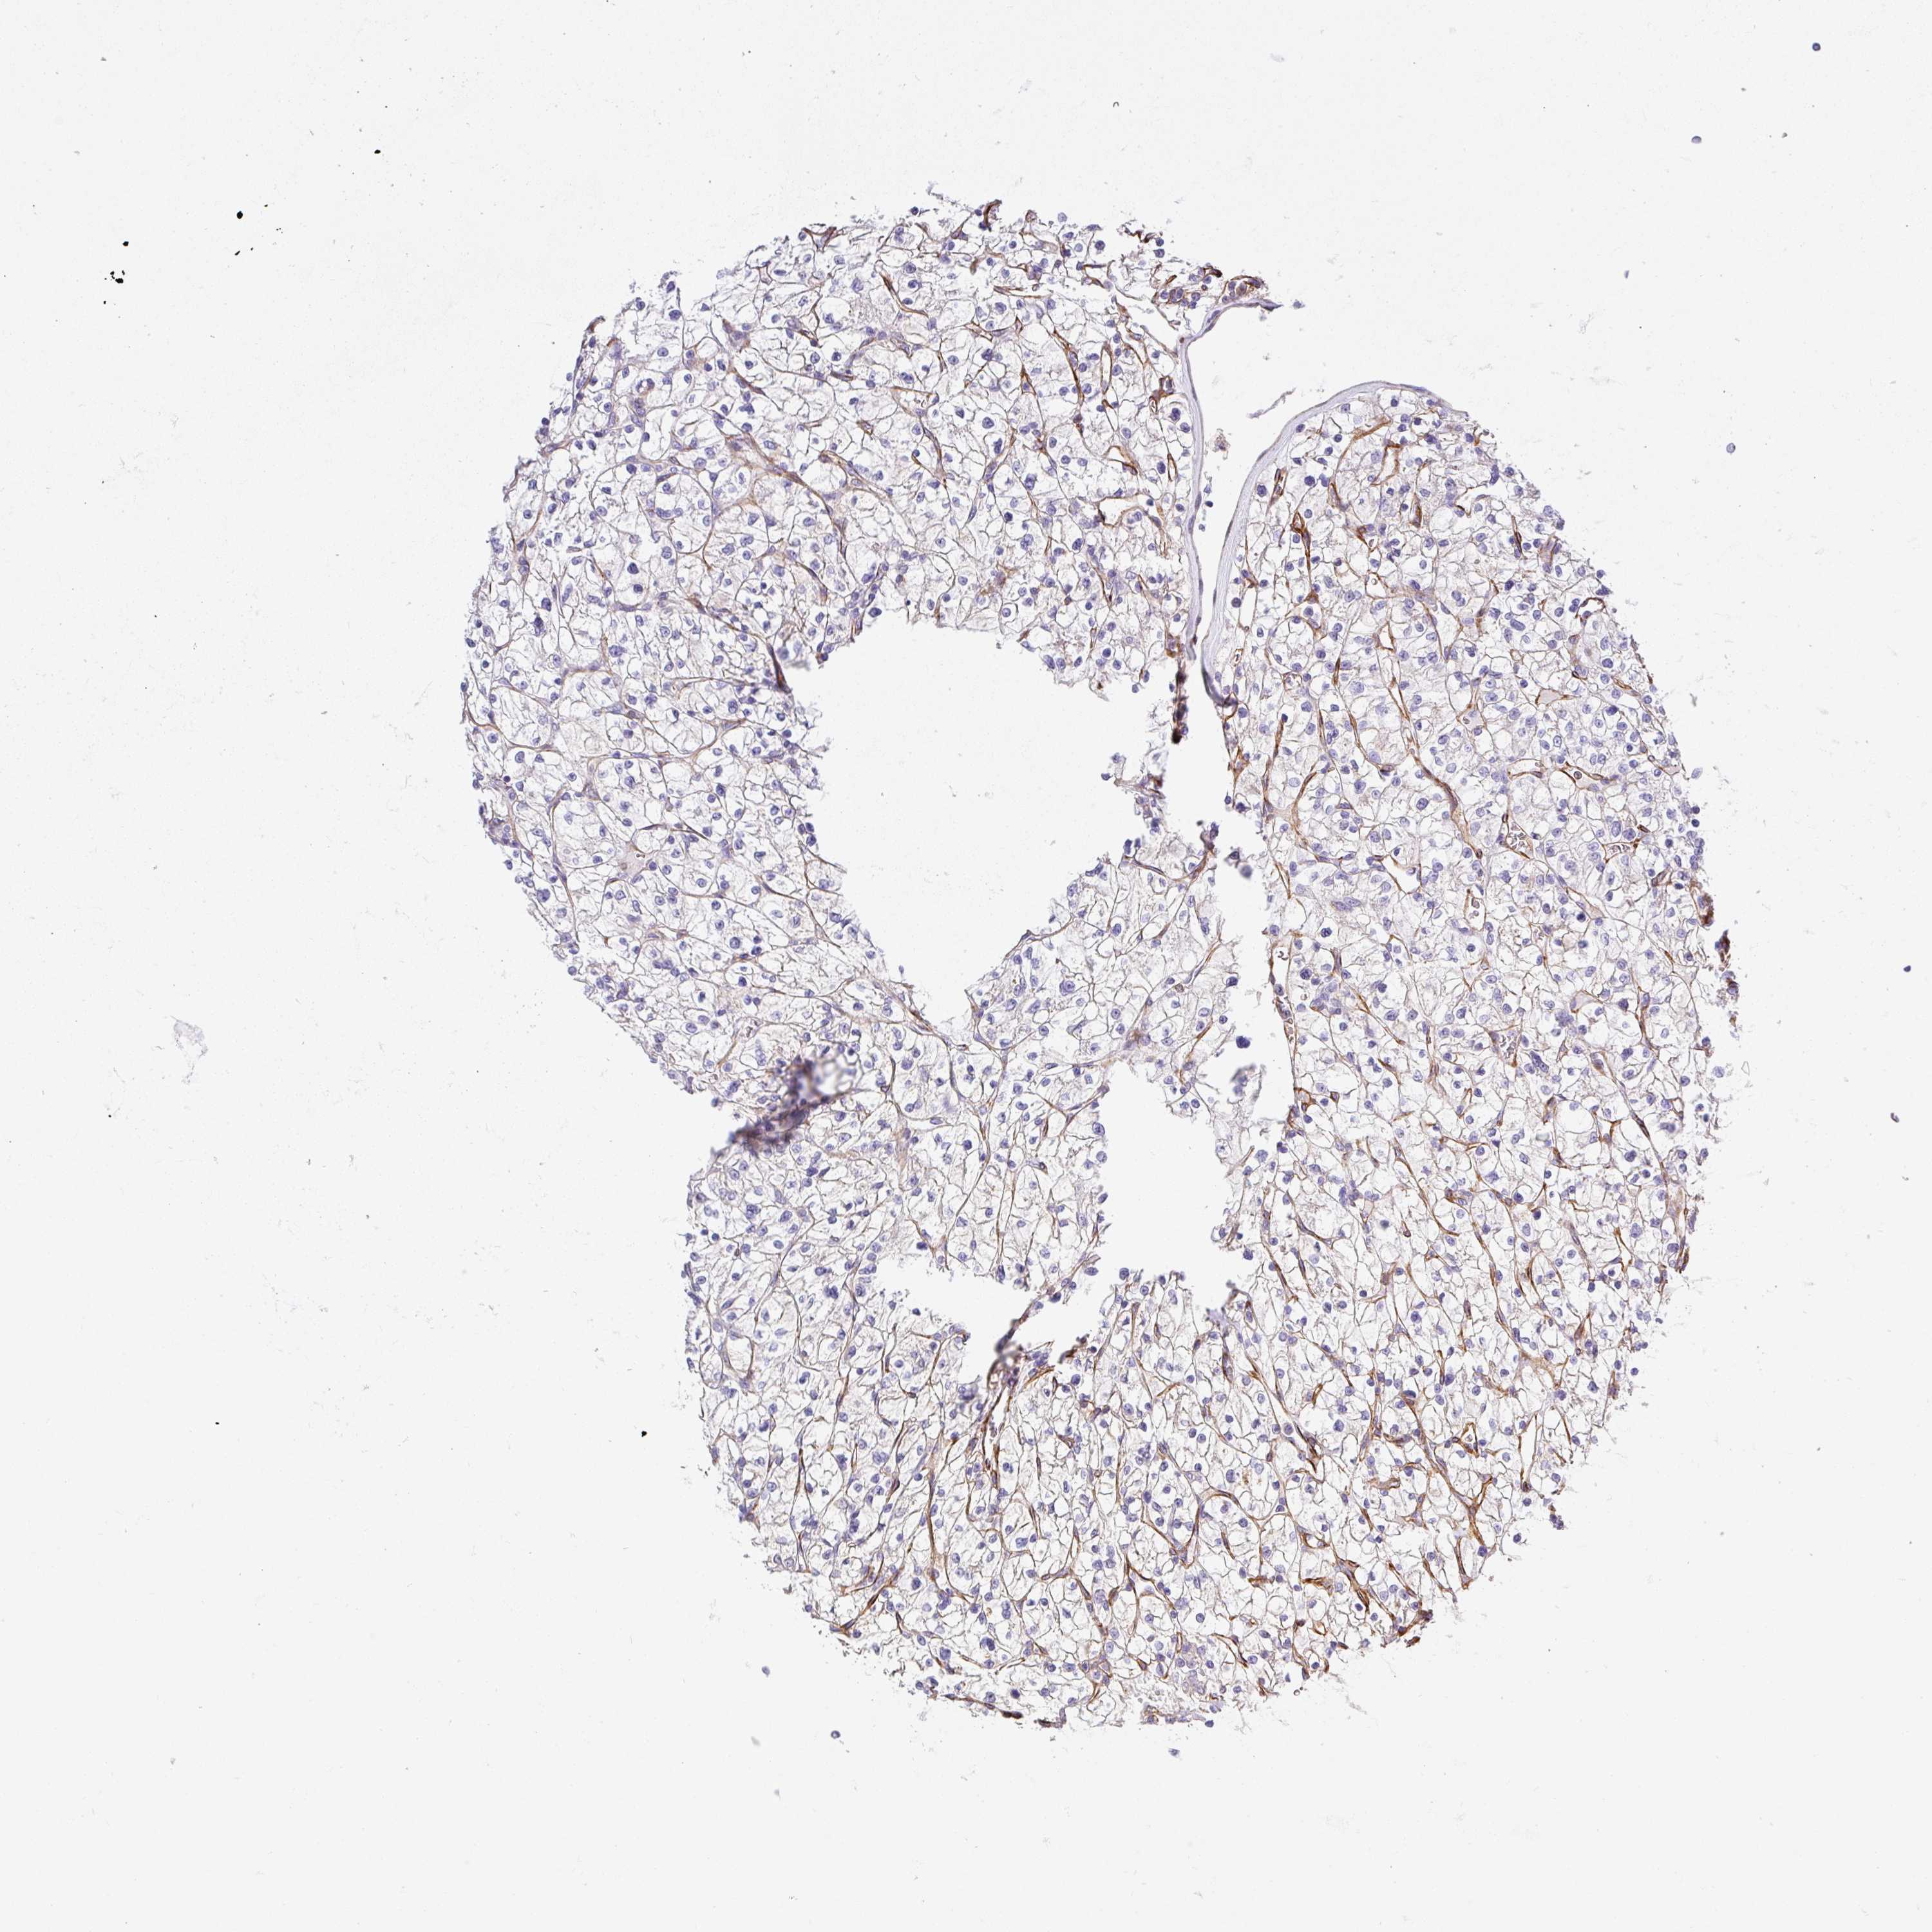

KIDNEY RENAL CLEAR CELL CARCINOMA (VALIDATION) - Interactive survival scatter ploti

The Survival Scatter plot shows the clinical status (i.e. dead or alive) for all individuals in the patient cohort, based on the same data that underlies the corresponding Kaplan-Meier plots. Patients that are alive at last time for follow-up are shown in blue and patients who have died during the study are shown in red.

The x-axis shows the expression levels (FPKM) of the investigated gene in the tumor tissue at the time of diagnosis. The y-axis shows the follow-up time after diagnosis (years). Both axes are complimented with kernel density curves demonstrating the data density over the axes. The top density plot shows the expression levels (FPKM) distribution among dead (red) and alive patients (blue). The right density plot shows the data density of the survived years of dead patients with high and low expression levels respectively, stratified using the cutoff indicated by the vertical dashed line through the Survival Scatter plot. This cutoff is automatically defined based on the FPKM cutoff that minimizes the p-score. The cutoff can be changed by dragging the vertical line or by entering a cutoff value in the square labeled "Current cut-off".

Under the Survival Scatter plot the p-score landscape (black curve; left axis) is shown together with dead median separation (red curve; right axis). Dead median separation is the difference in median mRNA expression between patients who have died with high and low expression, respectively. It is calculated as follows: median FPKM expression of dead patients with high expression - median FPKM expression of dead patients with low expression. This is intended to aid the user in visually exploring custom cutoffs and the associated p-scores and dead median separation.

Individual patient data is displayed and can be filtered by clicking on one or more of the category buttons on the top of the page. Categories describing expression level and patient information include: high, low, alive, dead, female, male and tumor stages. The scale of the x-axis can be toggled between linear and log-scale by clicking on the "x log" button. Mouse-over function shows TCGA ID, patient information and mRNA expression (FPKM) for each patient.

& Survival analysisi

Kaplan-Meier plots summarize results from analysis of correlation between mRNA expression level and patient survival. Patients were divided based on level of expression into one of the two groups "low" (under cut off) or "high" (over cut off). X-axis shows time for survival (years) and y-axis shows the probability of survival, where 1.0 corresponds to 100 percent.

SLC25A17 is not prognostic in Kidney Renal Clear Cell Carcinoma (validation)

Best expression cut offi

Based on the FPKM value of each gene, patients were classified into two groups and association between prognosis (survival) and gene expression (FPKM) was examined. The best expression cut-off refers the FPKM value that yields maximal difference with regard to survival between the two groups at the lowest log-rank P-value. Best expression cut-off was selected based on survival analysis .

When clicking on this number, the vertical dashed line indicating cut-off, the interactive survival plot, and the Kaplan-Meier curve will be adjusted to show results based on the best expression cut-off.

: 10.62

TCGA RNA samplesi

RNA-seq data is reported as average FPKM (number Fragments Per Kilobase of exon per Million reads), generated by the The Cancer Genome Atlas (TCGA) .

Normal distribution across the dataset is visualized with box plots, shown as median and 25th and 75th percentiles. Points are displayed as outliers if they are above or below 1.5 times the interquartile range. FPKM values of the individual samples are presented next to the box plot.

Average pTPM 13.0

Number of samples 100